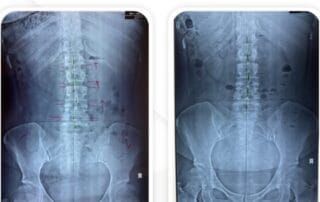

Vlife Medical was born from a strong desire to provide integrated healthcare services that offer pain solutions, sustainable results and renew your life. We are a team of licensed medical professionals under the supervision of relevant domestic services who develop a traditional evolution towards a modern approach in treating spine and musculoskeletal problems.